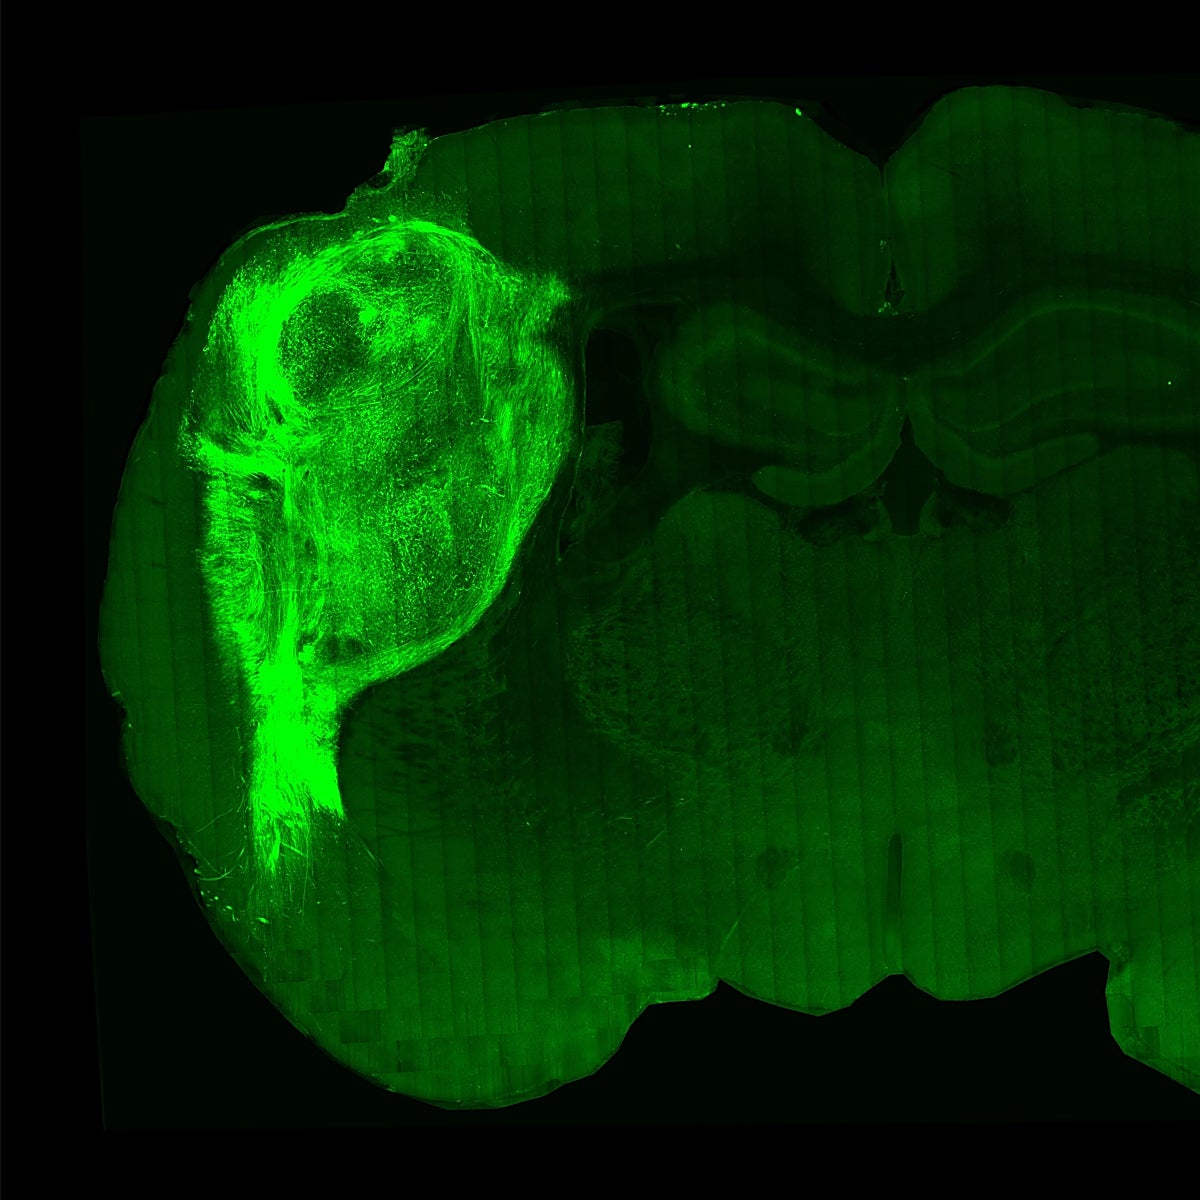

No es la primera vez que la medicina regenerativa obra el 'milagro' de fabricar órganos en el laboratorio a partir de células. Desde que se descubrió que se podía dar marcha atrás en reloj biológico y reprogramar células adultas para convertirlas en cualquier tipo celular del organismo, la lista de 'mini órganos' que crecen en una placa de cultivo no ha dejado de crecer. El resultado no es perfecto, pero está ayudando a entender numerosas enfermedades. A partir de la células adultas, se han fabricado corazones, riñones, pulmones, partes de un intestino y hasta minicerebros. Sin embargo, reproducir una estructura más sencilla, como parece el folículo capilar, no se había logrado aún.

En realidad el folículo piloso es una estructura muy compleja donde nace el pelo. Alojado en la dermis, permite el crecimiento del cabello, gracias entre otras, a la concentración de células madre. En su formación desde el estado embrionario se producen interacciones entre la capa más externa de la piel y el tejido conectivo, un diálogo complejo que no se había descifrado bien. Por eso, hasta ahora no se había logrado reproducir cabello en una placa de cultivo.